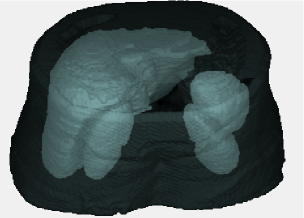

Figure 2 shows multi-object 3D ASMs for abdominal organs. Note that skins are also considered in the s to restrict the search space. Note also that mean shapes of the objects do not have any overlapped region with other mean shapes of the objects. Because, in training part, we select the objects such that , implying that there is no overlaps across the objects. This fact leads to , as each mean shape is created independently and alignment of the shapes of objects does not affect the distribution of objects in the mean shape due to the nature of the 7-parameter affine transformation : . Objects are not aligned individually, hence, their spatial relations before and after alignment does not change.

|

Once the is created, the next step is to initialize the segmentation process by locating the into any given subject image, with proper scale, translation, and orientation parameters, described in the following sections. After the objects in the given image are recognized, local constraints of the shape points in are incorporated into the hybrid delineation algorithm called iterative graph-cut active shape model, see [8] for details.